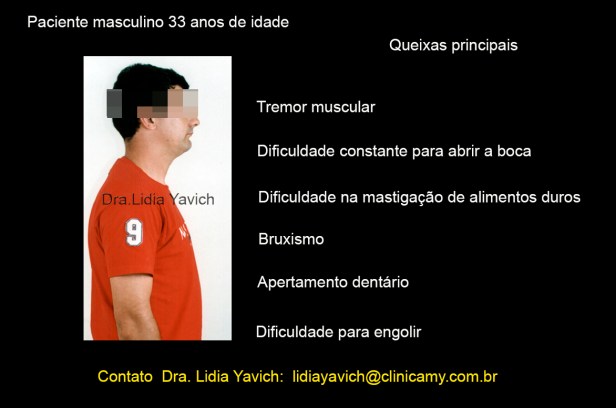

Paciente masculino de 33 anos de idade se apresenta na consulta relatando fortes dores nos temporais, dor no pescoço, dor facial inespecífica, dor nos ombros, zumbidos e relata também que vem sentindo adormecimento e formigamento nas mãos.

O paciente também se queixa de estalos na articulação temporomandibular do lado esquerdo. Relata sensação de diminuição auditiva, mesmo que a audiometria apresenta-se dentro dos valores normais.

Refere tremores musculares na região das bochechas, e dificuldade constante para abrir a boca.

O paciente não apresenta limitação na abertura bucal, mas para abrir desvia a mandíbula para o lado esquerdo.

Sente dor para mastigar alimentos duros, refere que só consegue se alimentar com alimentos moles.

Relata que qualquer refeição implica esforço e não uma atividade agradável, mesmo com alimentos que ele gosta.

Refere bruxismo e apertamento dentário. Diz que sente também dificuldade para deglutir.

O paciente apresenta um perfil retrusivo, mas isso NÃO FOI O MOTIVO DA CONSULTA, o paciente não estava preocupado pela estética, mas sim com A DOR.